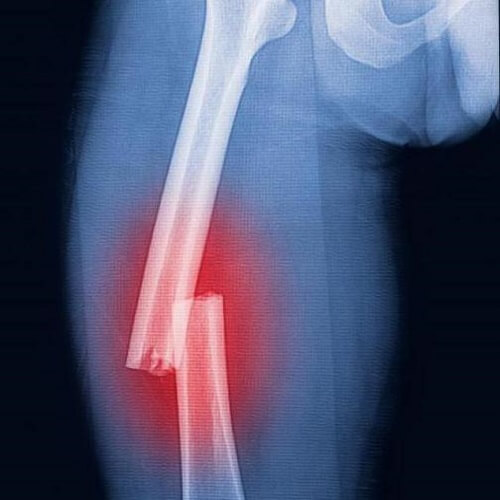

Перелом костей одна из самых неприятных травм, которые могут произойти с человеком. Редко можно встретить человека, который бы ничего себе не ломал в течении жизни.